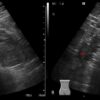

– Thận xoa trục, 2 cực dưới thận liên tục với nhau vắt ngang qua phía trước cột sống bởi nhu mô thận hay tổ chức xơ.

– Trên lát cắt dọc: không thấy rõ ranh giới cực dưới 2 thận.

– Trên lát cắt ngang qua đường giữa: 2 thận dính nhau, vắt ngang qua cột sống, phía trước động mạch chủ bụng.

– Có thể kèm theo các bất thường bất thường đường bài xuất, thận đôi, sỏi, nang thận hoặc u thận, sỏi gây giãn đường bài xuất.

=> Case lâm sàng 1: